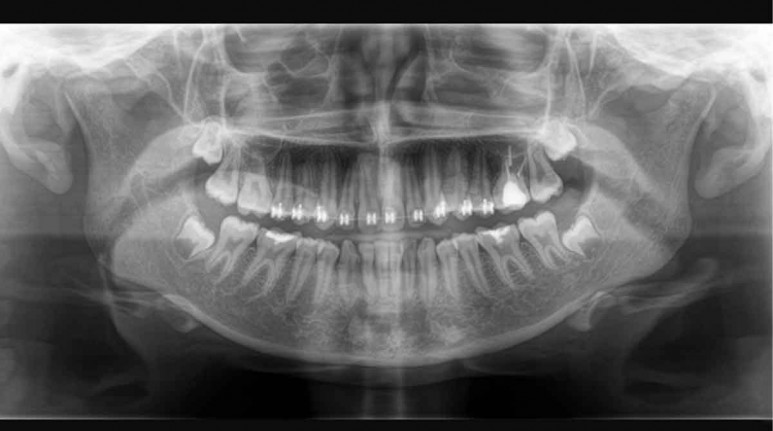

Sin lugar a dudas, existen muchos factores que pueden causar esta enfermedad, pero en años recientes, se han encontrado similitudes en algunos estudios del Alzheimer y un patógeno que se encuentra en la Periodontitis crónica, o enfermedad de las encías, este agente microbiano fue llamado Porphyomonas gingivalis. Este patógeno también fue encontrado en cerebros de personas que padecían Alzheimer.

El Dr. David Reynolds, el director científico del Alzheimer’s Research UK, menciona que ‘‘Anteriormente, la bacteria P. gingivails asociada con la enfermedad de las encías se habría encontrado en el cerebro con Alzheimer, pero aún no está claro qué papel, si es que tiene alguno, juega en el desarrollo de la enfermedad’’, en resumen, aunque se hayan encontrado similitud en que ambas enfermedades provocan invasión en el cerebro, aún hay más pruebas por hacer. También se detectaron niveles altos de amiloide, esta proteína es distintiva del Alzheimer.

Descubrir esta relación es una sólida prueba de que hay una oportunidad de investigación, y si bien antes no existían indicaciones suficientes para impulsar su estudio, al día de hoy la casualidad se dejó de lado y la comunidad científica ha puesto manos a la obra. Incluso, para reafirmar la importancia de realizar más estudios, el equipo que lleva la investigación también encontró enzimas tóxicas, gingipainas, estas sustancias son originadas por las bacterias que alcanzan el cerebro de una persona con Alzheimer, y se le relacionan con un par de proteínas encontradas en esta enfermedad (Tau y ubiquitina).

También se ha encontrado evidencia de gingipainas tóxicas en cerebro de personas fallecidas, pero que nunca fueron diagnosticadas con Alzheimer. Ahora bien, nunca se ha sabido si la relación es que la demencia conduce a un deficiente cuidado bucal, o si la infección P. gingivalis produce Alzheimer.